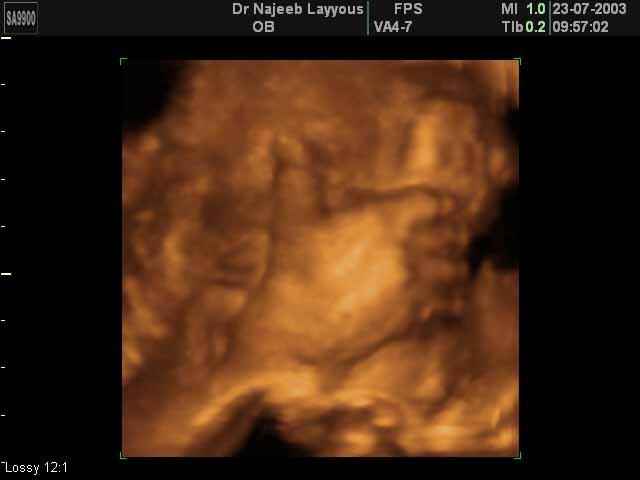

3D Ultrasound Scan Photos of Fetal Limbs | Dr N Layyous

3D Fetal Limbs Ultrasound Scan Photos